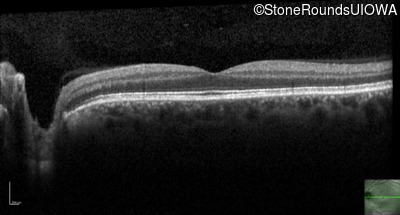

Optical Coherence Tomography - Right - 20/400 sc

Exemplar / OCT Stack